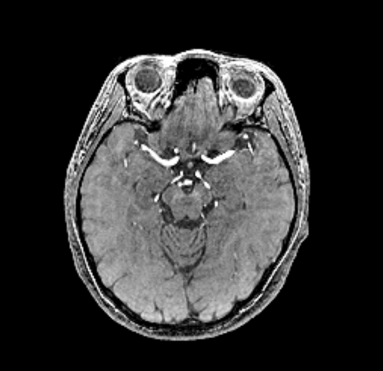

Various medical imaging techniques, such as computed tomography angiography (CTA), magnetic resonance angiography (MRA), and digital subtraction angiography (DSA) can be used to obtain images of the brain. DSA is the most sensitive method for diagnosing intracranial IAs; however, it is invasive and time-consuming. Although CTA scans are efficient, distinguishing the details of vessels and aneurysms using CTA remains difficult. TOF-MRA is a less invasive examination and has a high sensitivity for diagnosing IAs. Therefore, we decided upon TOF-MRA as a suitable technique for preoperative examination. However, our proposed pipeline is not affected by the type of medical image, as it is based on reconstructed surface models.

We collected TOF-MRA image sets of 103 patients with 114 aneurysms. Each set contains at least one IA, and 2D images sliced by . Our dataset does not include small aneurysms (<3.00 mm), because our objective is to segment the aneurysms requiring surgery. We calculated the size of each aneurysm based on maximum diameter, and Figure 5 shows the distribution (Mean: 7.49 mm, SD: 2.72 mm; Range: 3.48–18.66 mm) of aneurysm sizes on our dataset. In terms of IA type, most of our data were saccular aneurysms, and one fusiform aneurysm was included, but no dissecting aneurysm. Another special case was that we treated two aneurysms very close together as being one. We annotated the aneurysm portions on both the entire surface models of the brain arteries and on TOF-MRA images to generate a ground truth for classification and segmentation for training neural networks. It took a total of three experts 21 working days to perform this task. We used five-fold cross-validation to conduct our experiments. A total of 103 sets were shuffled and divided into five subsets, of which four were used as the training data, and one was used as testing data. This study design was approved by an appropriate ethics review board.